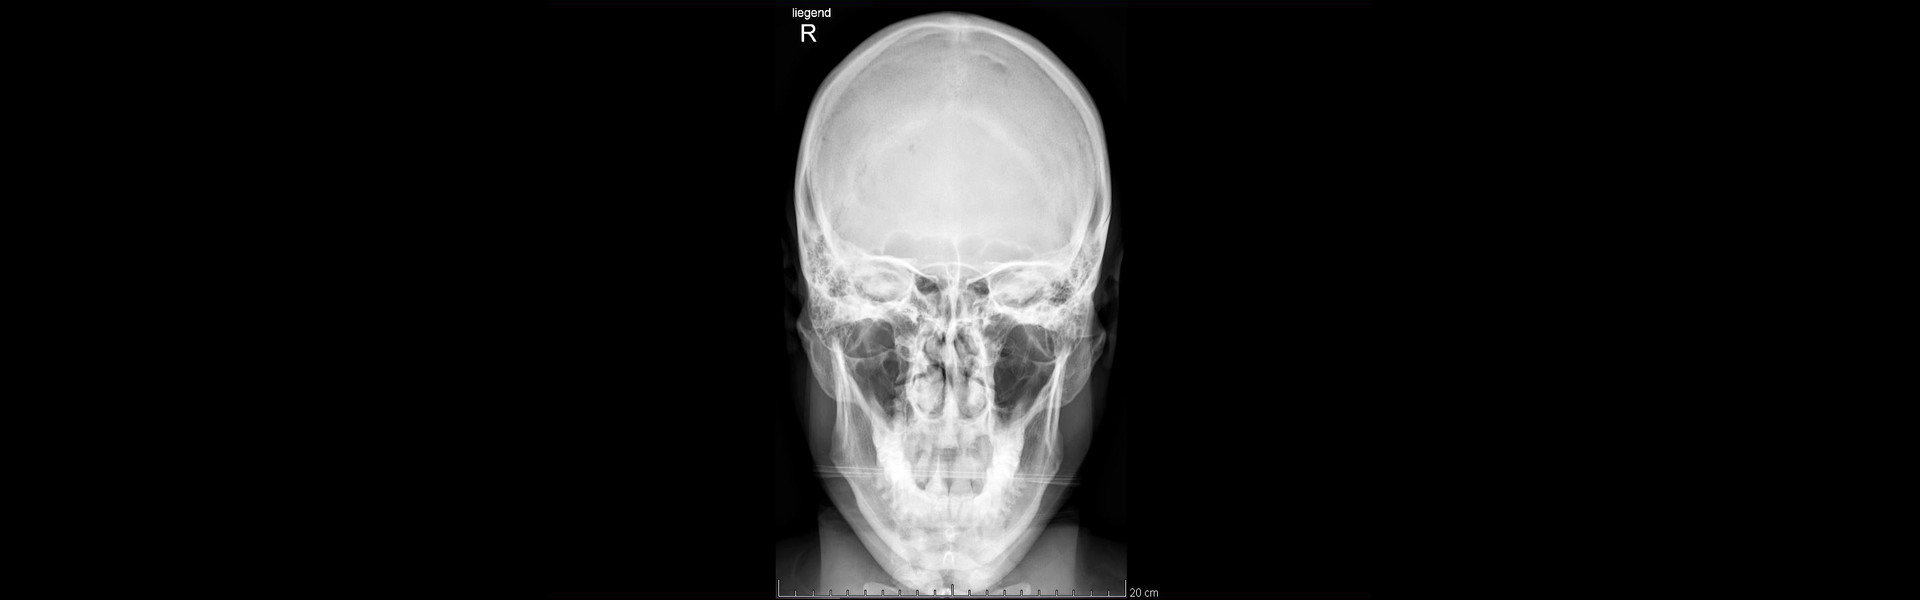

Bilder zu zeigen, wo eine Skitour auch mal im Krankenhaus und nicht zwangsweise bei einem Weißbier auf der Sonnenterrasse enden darf, die Abfahrt auch mal 1300 Hm Bruchharschgewürge bedeuten kann, wo definitiv gar nichts staubt außer die Wundkompressen, die man sich abends auf das verrenkte Knie wickelt, mag zwar nicht Publikumswirksam sein aber es beruhigt mein Gewissen. Meinem Wunsch auch mal ein Lächeln zu zeigen, wo ein Zahn fehlt und ein eingetrockneter Bluttropfen noch an der Nase klebt möchte ich hiermit ebenfalls nachkommen.